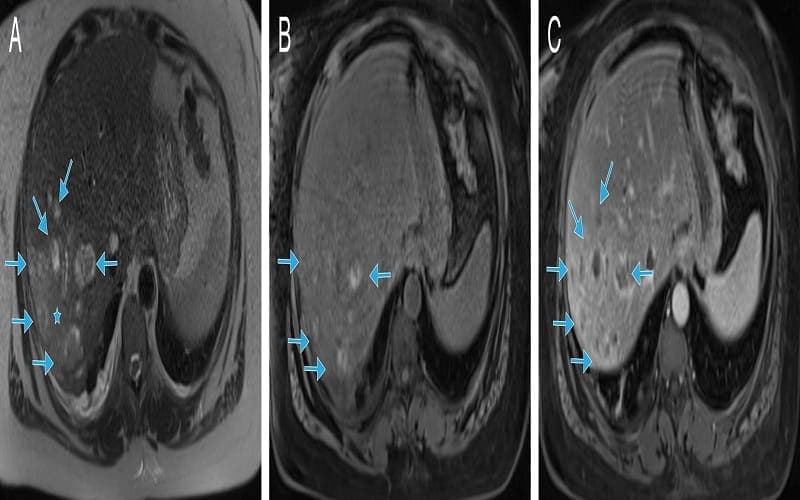

- Chẩn đoán hình ảnh: Siêu âm và CT có tiêm thuốc cản quang là phương tiện quan trọng. Trên CT, áp xe gan do Klebsiella thường là ổ đơn độc, kích thước >5 cm, hay nằm ở thùy phải, có thể dạng đặc hoặc đa ổ, dễ thấy khí trong ổ mủ; bệnh nhân gan tiểu đường thường có nhiều tổn thương gan hơn.